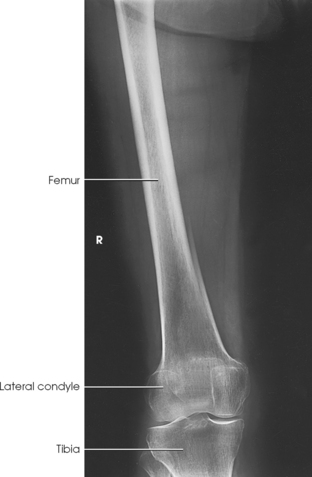

Structures shown: The resulting image shows an AP projection of the femur, including the knee joint or hip or both (Figs. 6-165 and 6-166).